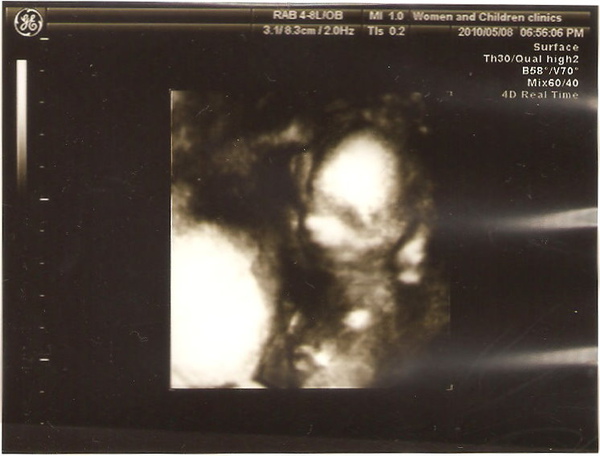

現在看還不準的臉